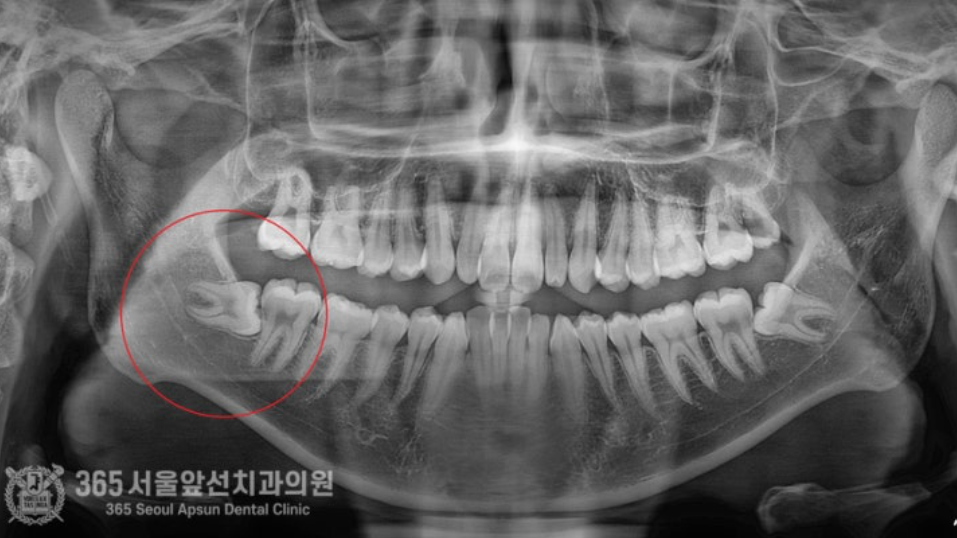

치아교정 전에 양쪽 매복사랑니 발치하고 싶어요. 안녕하세요. 간석동치과 365서울앞선치과의원입니다. 오늘 소개해드릴 치료 증례는 아래턱 수평 매복 사랑니 발치 증례입니다. 상기 환자분께서도 그러한 이유에서 사랑니 발치를 원하셔서 진행하기로 했습니다 ㅎㅎ 촬영일시 : 2024.08.13. 처음 내원 당시 엑스레이 사진입니다. 입안에서 오른쪽 아래턱(사진상 왼쪽 아래 빨간원)에 수평으로 매복된 사랑니가 관찰됩니다. 촬영일시 : 2024.08.13. 정밀한 작은 엑스레이를 촬영했습니다. 사진 상에서 아래쪽에 신경관이 지나가는게 관찰됩니다. 주의해서 발치해야겠습니다. 촬영일시 : 2024.08.13. 발치를 시작한지 6분만에 발치를 완료했습니다. 빠르고 정확한 발치를 통해 환자분의 고통을 줄여드릴 수 있었습니다 ㅎㅎ 촬영일시 : 2024.08.13. 매복사랑니를 세 조각으로 잘라서 발치를 진행해드렸고, 깔끔하게 절단된 사랑니 조각들이 보입니다. 빠르고 정확한 발치에 환자분께서도 만족하셨습니다. 오늘은 6분만에 아래턱 매복 사랑니 발치를 완료한 치료 증례를 소개해드렸습니다. 앞으로도 더 좋은 치료 증례로 찾아뵙겠습니다. 간석동치과 365서울앞선치과의원이었습니다. 감사합니다! [ 치료기간: 2024년 8월13일 ] ※ 365서울앞선치과의원의 모든 포스팅은 각 진료과 의료진이 직접 작성합니다. 365서울앞선치과의원 블로그의 임상 케이스 게시물은 환자분께 의학적으로 정확하고 상세한 정보를 드리기 위해 각 진료과 의료진이 직접 작성하며, 모든 증례 사진은 본원 의료진이 직접 시술한 증례를 촬영한 것으로, 의료법 제23조, 제56조에 의거하며 환자분의 동의를 얻어 포스팅에 사용하였습니다. 또한 해당 케이스는 본 환자분의 치료 결과이며, 환자 상태에 따라 치료의 결과는 달라질 수 있습니다. |